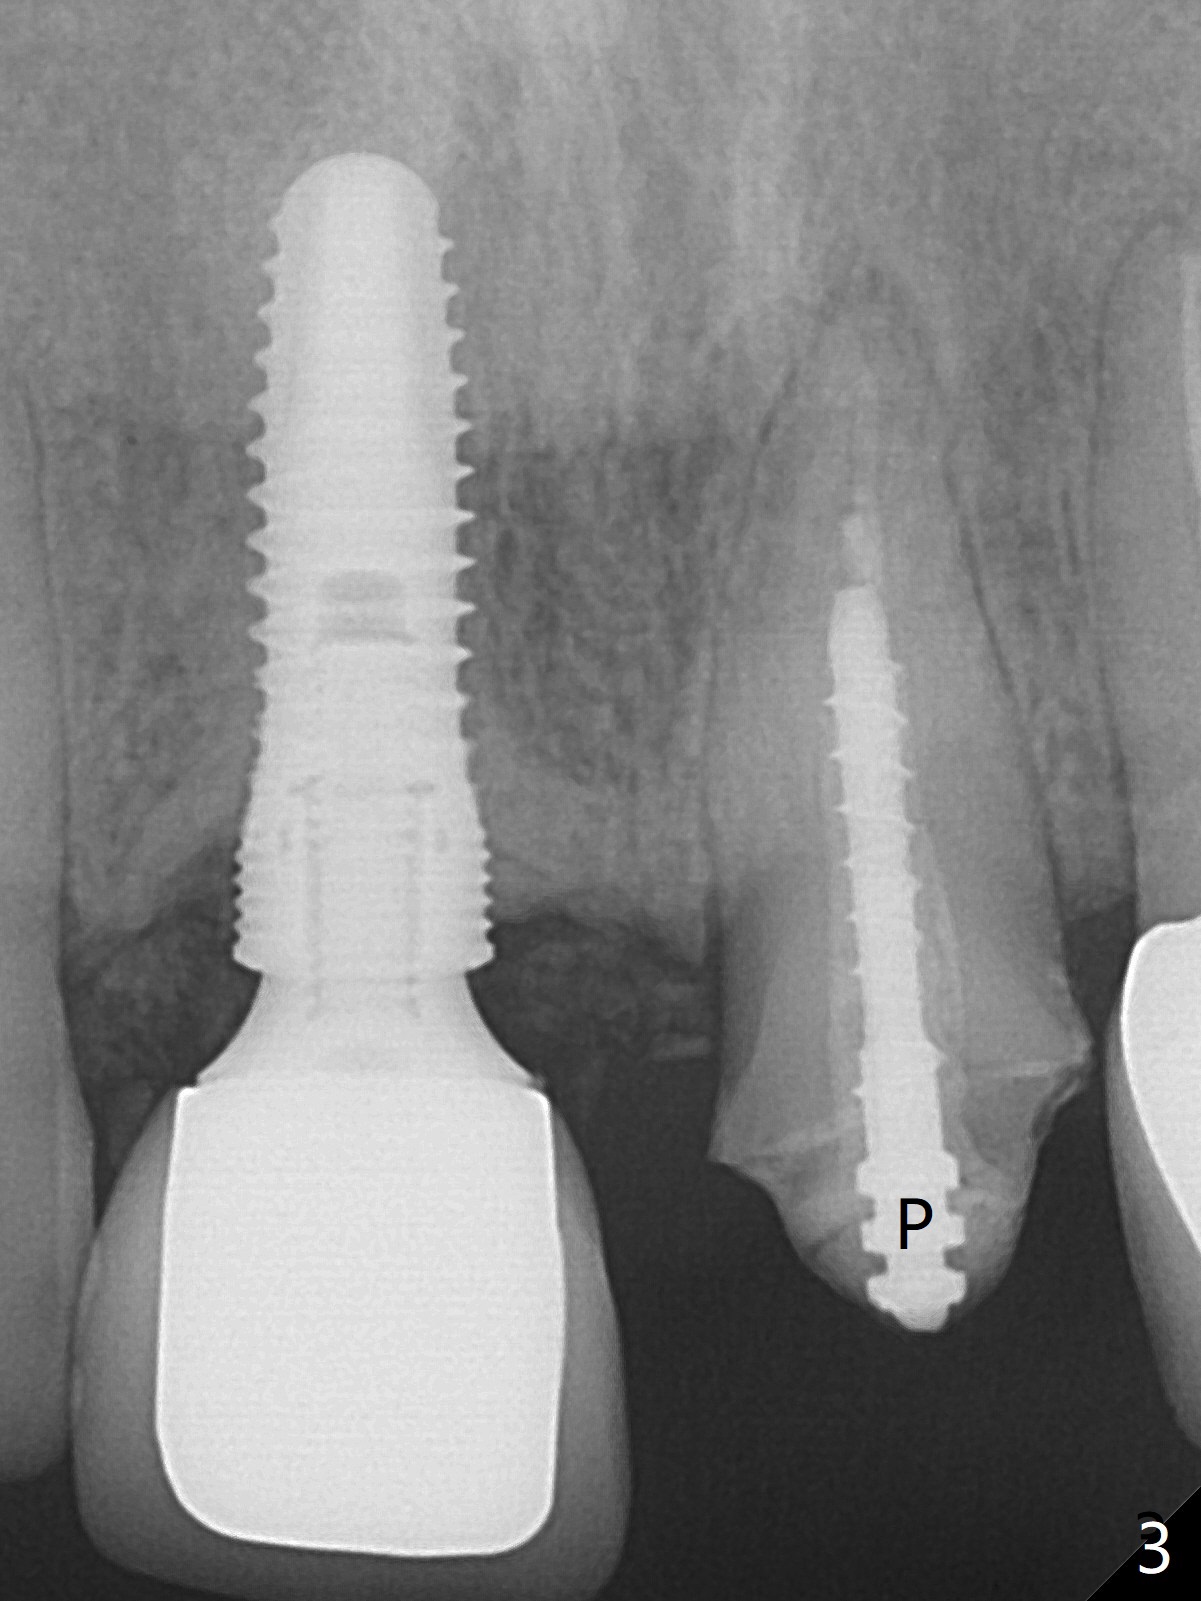

When the 44-year-old woman returns, the crown dislodges from #9 with palatal porcelain chip (Fig.1). Although the post is in place as compared to its dislodgement last visit, it is short and pointed (Fig.2,3 P). Because of the anterior deep bite (Fig.4), an implant restoration may not provide advantage; a new build-up is fabricated (B-U) for a new crown (Fig.5-6). The existing crown is reinserted for shade comparison (Fig.7 C). The gingiva at #8 and 9 is healthy, whereas that at #10 is not (Fig.8). PA taken 5 months later shows that the crown at #10 looks normal (Fig.9).